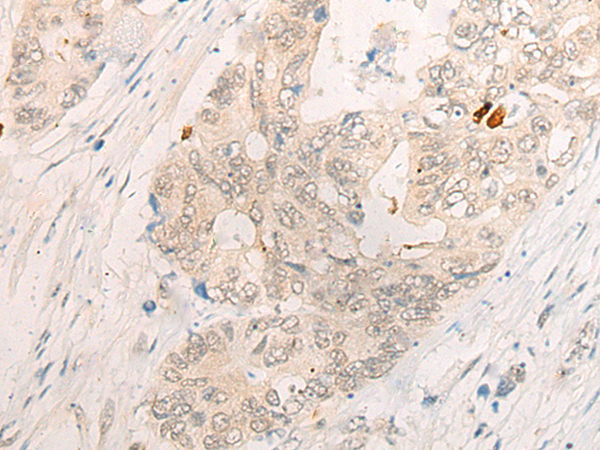

分类: 科研抗体货号: P06328别名: PAP1应用: WB,IHC反应种属: Human, Mouse